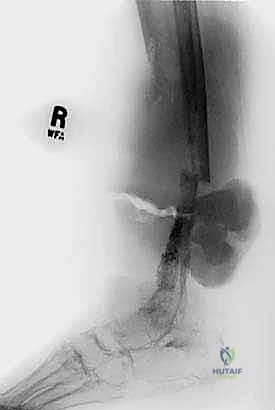

- الأشعة السينية (X-ray): الخطوة الأولى لتقييم العظام وتحديد نمط التدمير العظمي.

- الأشعة المقطعية (CT Scan): ضرورية لتقييم القشرة العظمية والتكلسات داخل الورم، وللبحث عن أي انتشار في الرئتين.

لضمان أخذ العينة من الجزء الأكثر تمثيلاً للورم وتجنب المناطق الميتة (Necrotic areas)، يستخدم الدكتور هطيف جهاز الأشعة المقطعية أو جهاز القوس المفلور (C-arm) لتوجيه الإبرة في الوقت الفعلي.